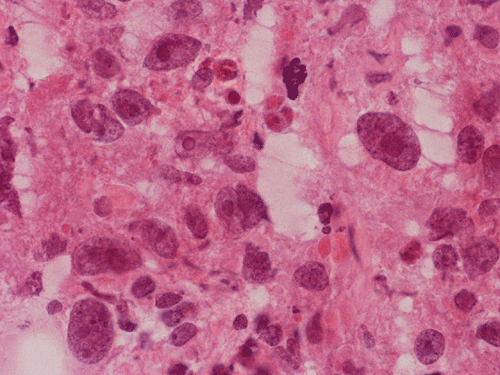

The volume of tissue received for examination amount to an aggregate of 4.0 x 2.0 x 1.5 cm in combined size. Grossly, the tissue is soft and has a creamy color with hemorrhage. The intraoperative cytologic preparation demonstrate a neoplasm composed with small to medium sized blue cells that smear out rather homgeneously and evenly. If you pay attention, there are some larger cells with a substantial amount of cytoplasm even at low magnification (Panel A). On high magnification, the nuclei are rather uniformly large, with high grade of pleomorphism, and almost all cells contain a distinct nucleoli. Apoptotic bodies and mitoses are frequent (Panel B). There are also large cells with prominent nucleoli and substantial amount of eosinophilic cytoplasm. These cells are suggestive of rhabdoid cells but none of them have the distinct inclusion body like cytoplasmic eosinophilic body of the rhabodid cells in atypical teratoid rhabodid tumor (Panel C). In the frozen section, both small to medium sized cells and cells with large nuclei with large, prominent, and eosinophilic nucleoli (Panel D and E). In the permanent sections, there is extensive necrosis (Panel F). The histology is in general agreement with that of frozen section except that the tumor cells appear to have more cytoplasm and more plemorphic, large nuclei with prominent nucleoli in comparison to the frozen section (Panel G). Large cells with substantial volume of cytoplasm, large, bizarre nucleoli and prominent, eosinophilic nucleoli are also noted (Panel H). There is a generalized degree of high grade pleomorphism. Results of immunohistochemistry are as follow:

Comment: This is an interesting case. Histologically, the overall morphology is consistent with a medulloblastoma with high grade of pleomorphism. Therefore, a diagnosis of large cell (anaplastic) medulloblastoma is the most likely diagnosis. The problem is the large cells with substantial amount of cytoplasm and large bizarre, eccentric nuclei with large nucleoli. These features raise the possibility of an atypical teratoid rhabdoid tumor (ATRT). These cells, if you observe carefully, lack the cytoplasmic, eosinophilic, inclusion body typical for rhabdoid cells. Nuclear wrapping is not readily seen. In fact, we did not find unmistakable nuclear wrapping until we looked at the immunohistochemistry for neurofilament. There are three immunohistochemical features in this case that are against a diagnosis of ATRT. First, vimentin is typically positive in most, if not all, tumor cells particularly those cells with rhabdoid changes. Second, most ATRT are positive for EMA. Third, the most powerful proof is the positive immunoreactivity of BAF47 which would be negative in ATRT. The negative result for desmin is helpful in ruling out the possibility of a rhabdomyosarcoma.

ATRT shares many features with large cell (anaplastic) medulloblastomas. First, most of them occur in infants and children but ATRT are a lot more common in children under three years of age. Both tumor are highly malignant. In fact, the rapid growth as documented in this case lead to the consideration of ATRT before surgery. Second, both entities are featured by large cells with large nuclei and prominent nucleoli. During frozen sections, it may be a difficult task to distinguish these tumors. The rhabdoid cells in ATRT my not be very characteristics and a medulloblastoma like component is not uncommon in ATRT. Also, the rhabdoid cells may not be that numerous and the pathologist has to search for them. The intraoperative cytologic preparations provide excellent cytologic and nuclear details. In general, cells of large cell medulloblastoma do not have the typical eccentric nuclei and cytoplasmic inclusion like bodies in comparison to ATRT. In addition, although the nucleoli are large, they are not as prominent and eosinophilic as in ATRT. Third, cells of ATRT tend to be more intact and large cell (anaplastic) medulloblastomas tend to have predominantly naked nuclei. Distinction of the two entities on permanent sections is usually not a major problem. It should be noted that ATRT are polyphenotypic. However, they are usually positive for EMA which is typically negative in medulloblastoma and its variants. The greatest help would be immunohistochemistry for BAF-47. This antibody recognizes the protein coded by INI1 gene which is the critical gene on chromoome 22q11.2. This gene is expressed in normal tissue as well as neoplastic tissue except in the tissue where this gene is deleted and ATRT is the prototype 9. In some cases of ATRT, the staining can be patchy. The genetic deletion can be confirmed by fluorescent in situ hybridization. In a minority number of cases, no chromosome 22q11.2 deletion is demonstrated. The gene can be sequence in order to search for mutation of the INI1 gene.